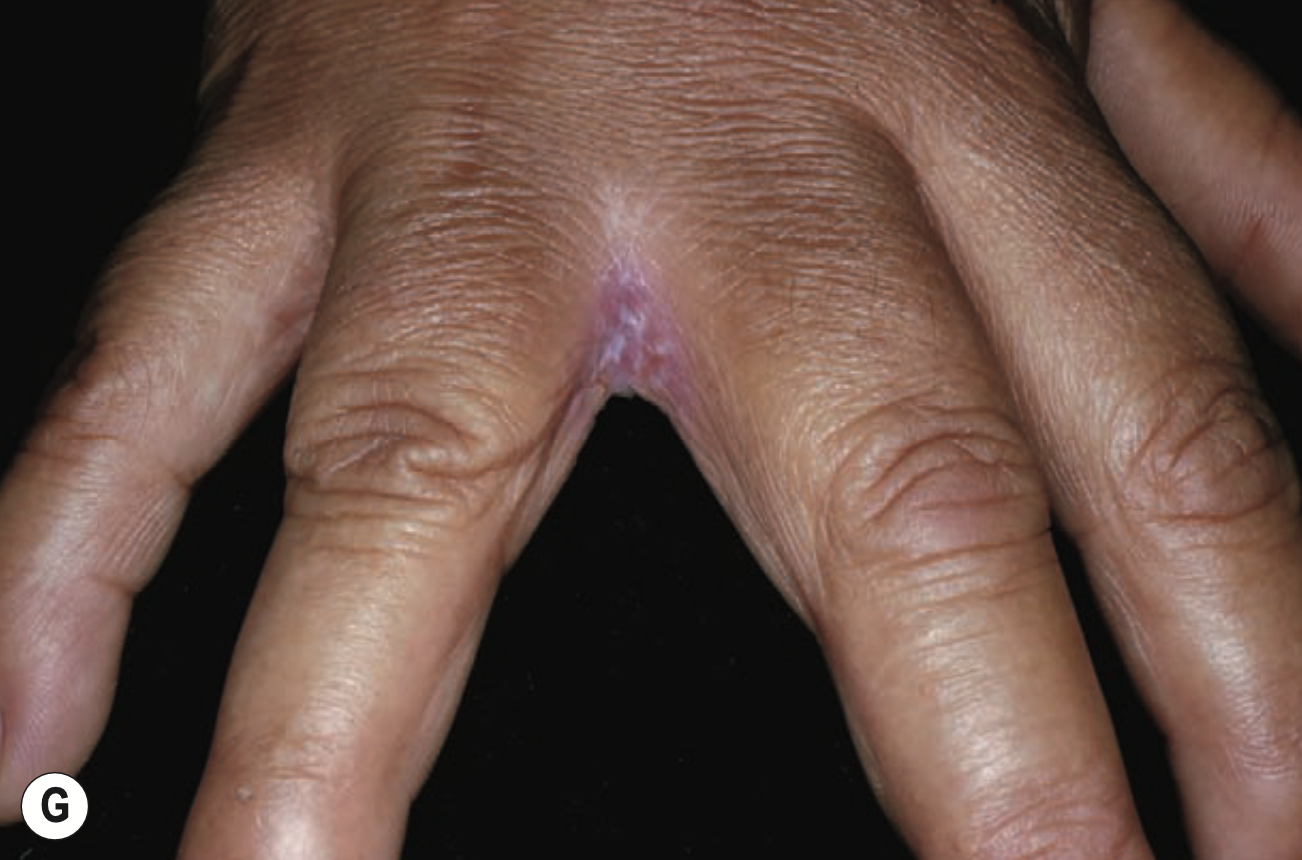

Erosio interdigitalis blastomycetica

Exposition fréquente à l’eau

Infection à Candida interdigitale

Surtout entre 3e et 4e doigt